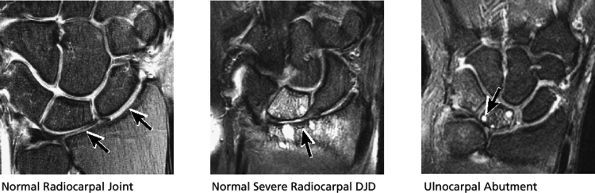

FIGURE 10.38 RADIOCARPAL JOINT.

(ulnolunate) impaction syndrome, whereas ulnar negative variance may be associated with Kienböck's disease of the lunate. With distal radioulnar joint instability, the ulna is dorsally or volarly subluxed with respect to the radius, usually due to severe TFC complex tears.